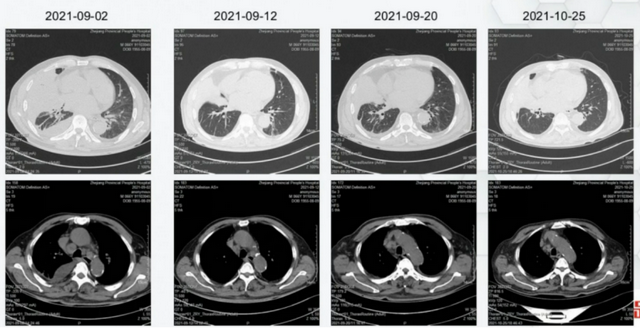

患者接受治疗后,原发灶与淋投合均显着 缩小。

图2:影像学评估效果